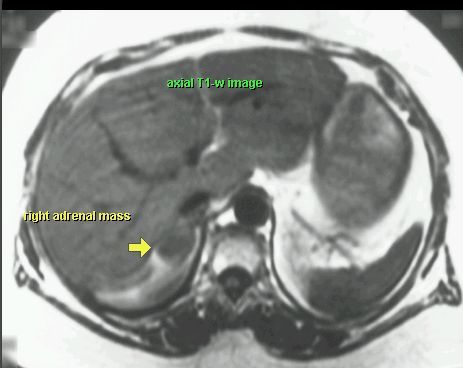

GRUCZOLAK NADNERCZA

MR